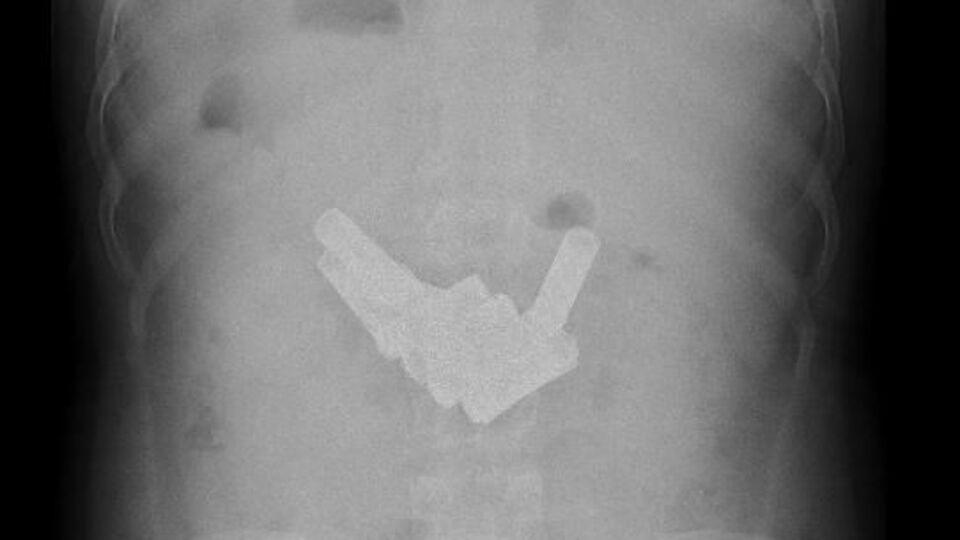

Manisa'da intihar teşebbüsünde bulunan bir mahkumun midesi ve ince bağırsaklarından 13 kalem pil çıkartıldı. Pil sayısı fazlalığı olarak tıp literatüründe ilk olduğu belirtilen hastanın sağlık durumunun iyi olduğu belirtildi

Manisa T Tipi Cezaevi'nde kalan 26 yaşındaki Ş.K., kaldığı koğuşta 13 pili art arda yutarak intihar teşebbüsünde bulundu. Fenalaşınca ambulansla Manisa Devlet Hastanesi'ne kaldırılan Ş.K.'nın çekilen röntgen filminde midesi ve bağırsaklarında 13 kalem pil olduğu saptandı. Genel Cerrahi Uzmanı Dr. Erdem Nalbant tarafından ameliyata alınan Ş.K.'nın midesi ve bağırsağından 13 kalem pil çıkartıldı. Sağlık durumunun iyi olduğu belirtilen Ş.K.'nın bir süre gözetim altında kaldıktan sonra taburcu edilerek tekrar cezaevine gönderileceği belirtildi.

Mahkumun ilk olarak karın ağrısı şikayetiyle geldiğini aktaran Manisa Devlet Hastanesi Genel Cerrahi Uzmanı Op. Dr. Erdem Nalbant, "Türkiye tıp literatüründe bu şekilde bol miktarda 13 pil yutup cerrahi operasyon gerçekleştirilen bir olay yok. Bu anlamda Türkiye'de ilk. 2016'da gerçekleştirilecek ulusal cerrahi kongresine bu olayı sunmayı düşünüyoruz. 11'i midede, ameliyat sırasında tespit ettiğimde bir tanesi ince bağırsağı geçmişti, biri on iki parmak bağırsağında idi" dedi.